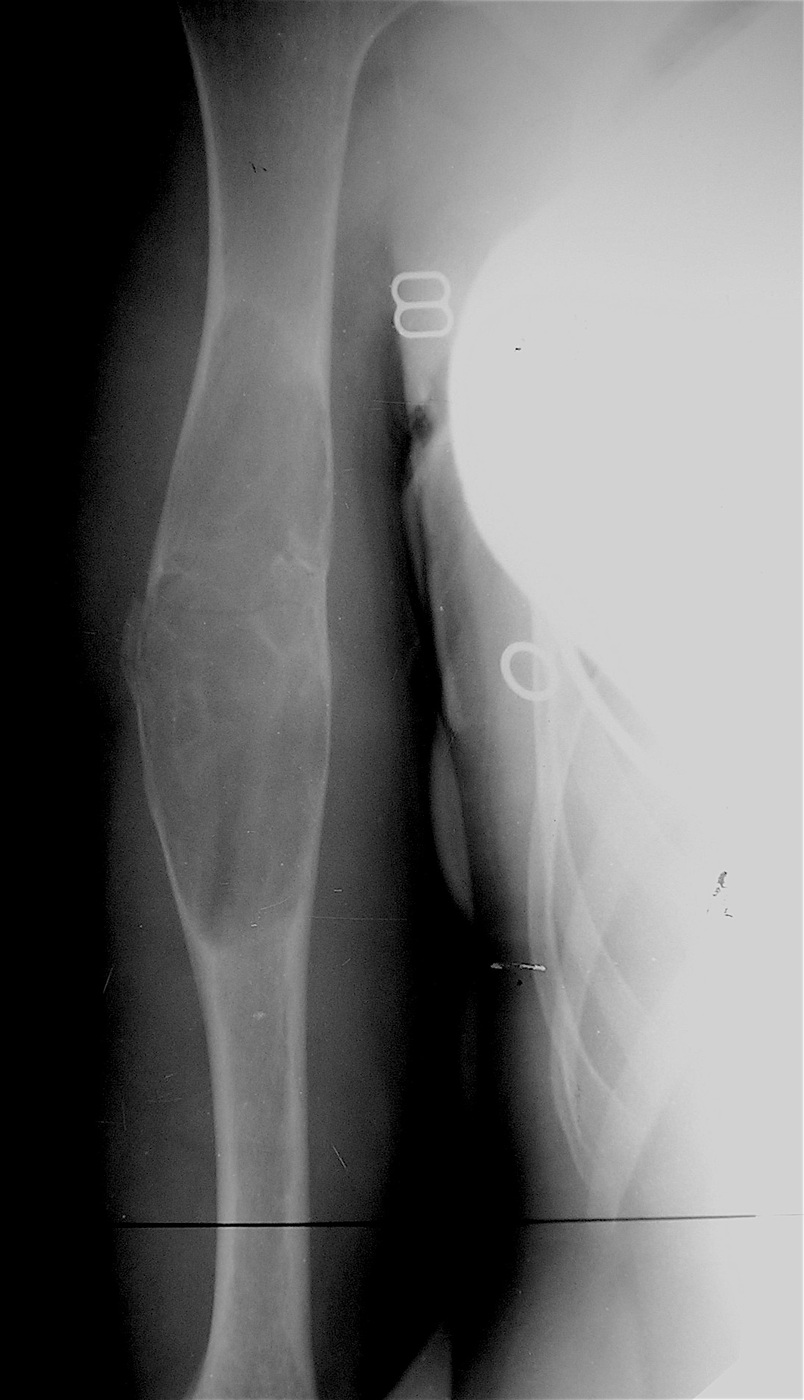

Закрытый, патологический перелом в с/з правой плечевой кости на фоне аневризмальной кисты диафиза правой плечевой кости.

Выполнена операция: экскохлеация кисты, остеосинтез титановыми эластичными стержнями и металлической скобой, аллопластика патологического очага материалом «Лиопласт».

Функция конечности сохранена, ребенок себя обслуживает.

Имеется укорочение правой верхней конечности  на 1,5 см за счет плеча.